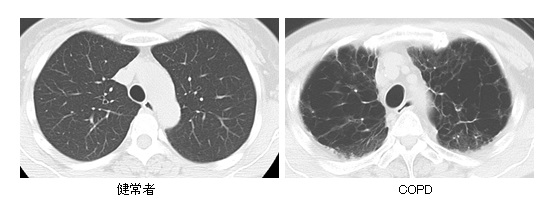

スパイロメトリー検査(肺活量検査)を行い診断します。(図2)検査は簡単で短時間で済みます。当施設では、他の呼吸器疾患を除外するために、精密呼吸機能検査や胸部X線およびCT検査等を組み合わせることで診断をより確かなものとし、重症度を決定しています。近年、注目される喘息とCOPDのオーバーラップ症例については、種々の血液検査、呼気ガス分析、喀痰検査などを併用することで診断します。また、その他の呼吸器疾患の合併症(気管支喘息や肺線維症、肺癌等)のほか、心疾患や鬱状態や糖尿病等のCOPDに合併する事の多い全身性疾患(併存症)も併せて診断します。

図2. 健常者(左)とCOPD患者さん(右)のスパイロメトリー。縦軸が息を吐くスピードを表しています。COPD患者さんでは息を吐くスピードがすぐに落ちてしまいます。気管支が狭くなっていることを示しています。